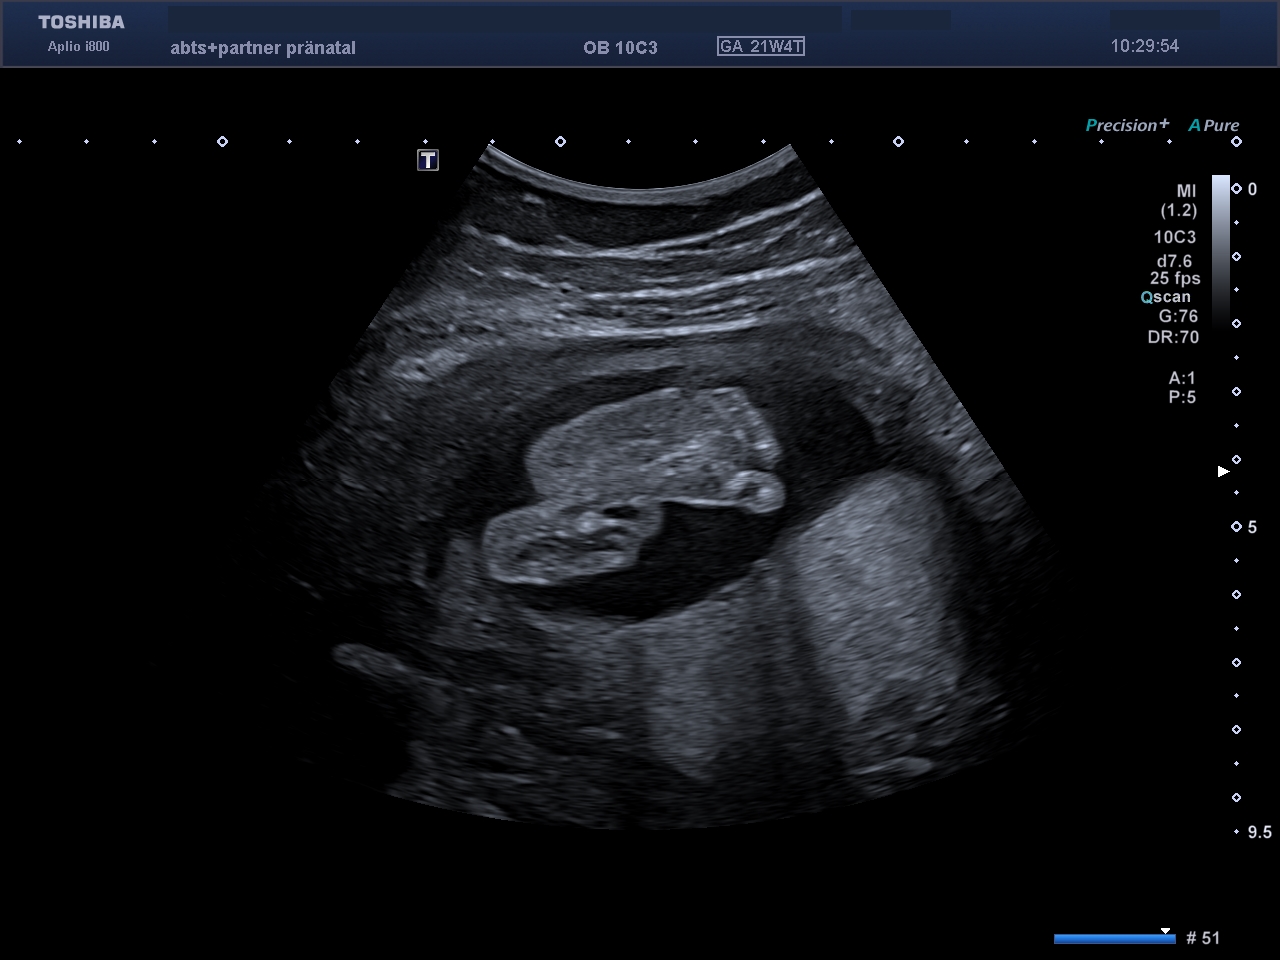

Das Baby in der Übersicht. So können Wachstum und Proportionen, Herzschlag und Gesicht gesehen werden.

Der kindliche Bauchumfang mit dem gefüllten Magen.